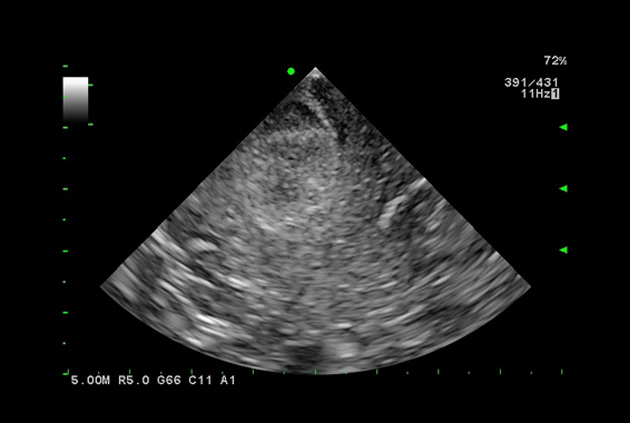

Contrast Harmonic Imaging (CHI)

Contrast-specific software is supported for use with contrast agents used with acoustic pressures from low to mid Ml. This is compatible with various transducers.